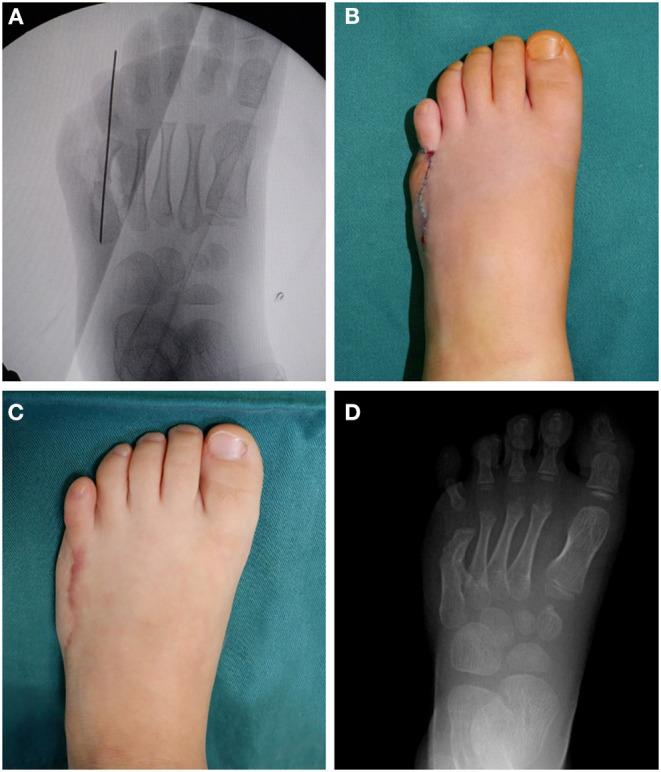

Polydactyly is a common deformity of the limbs, and excision of the extra digit has shown good results in the vast majority of patients. However, this treatment approach may not suitable for all cases of polydactyly. Some complex surgical procedures are required to treat rare forms of polydactyly and achieve satisfactory correction. Here, we report the use of on-top plasty technique for treating polydactyly between the 4th and 5th metatarsals with concomitant angulation of the 5th metatarsophalangeal joint. We performed the first osteotomy at the neck of metatarsal bone by "grafting" the distal polydactyly with the normal axis to the 5th metatarsal bone. Excision of the extra toe was accompanied by simultaneous restoration of the 5th toe axis and decrease in the width of the forefoot. Finally, both appearance and function could be improved. With this novel method, the complete osteoarticular structure and weight-bearing structure of foot were well-reconstructed. Based on the findings, we recommend that for the surgery of polydactyly, the beneficial parts should be preserved for reconstruction, and the tailored and personalized approach could be adopted.

多指畸形是一种常见的肢体畸形,绝大多数患者切除多余手指后效果良好。然而,这种治疗方法可能并不适用于所有多指畸形病例。治疗罕见类型的多指畸形并实现满意的矫正需要一些复杂的外科手术。在此,我们报告使用顶置成形术治疗第4和第5跖骨之间的多指畸形,并伴有第5跖趾关节成角。我们通过将具有正常轴线的远端多指“移植”到第5跖骨上,在跖骨颈部进行了第一次截骨术。切除多余脚趾的同时恢复了第5趾的轴线,并减小了前足的宽度。最终,外观和功能均得到改善。通过这种新方法,足部完整的骨关节结构和负重结构得到了良好重建。基于这些发现,我们建议对于多指畸形手术,应保留有益部分进行重建,并可采用量身定制的个性化方法。